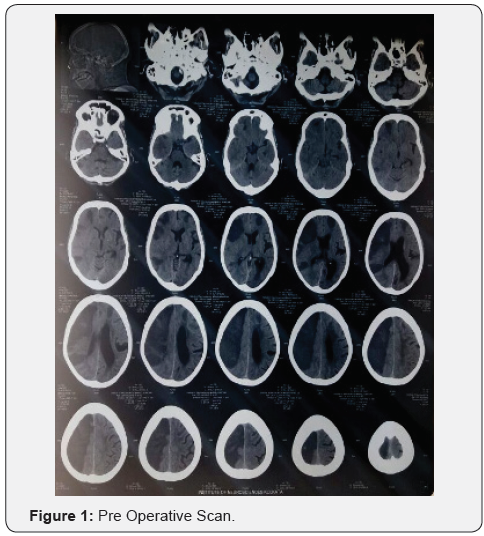

Ischemic area > 145 mL, even at early stages. Moreover, DWI ischemic volumes larger than 210 mL were found related to a 100% mortality in patients without surgical treatment Laboratory data [1] (Figures 1&2).